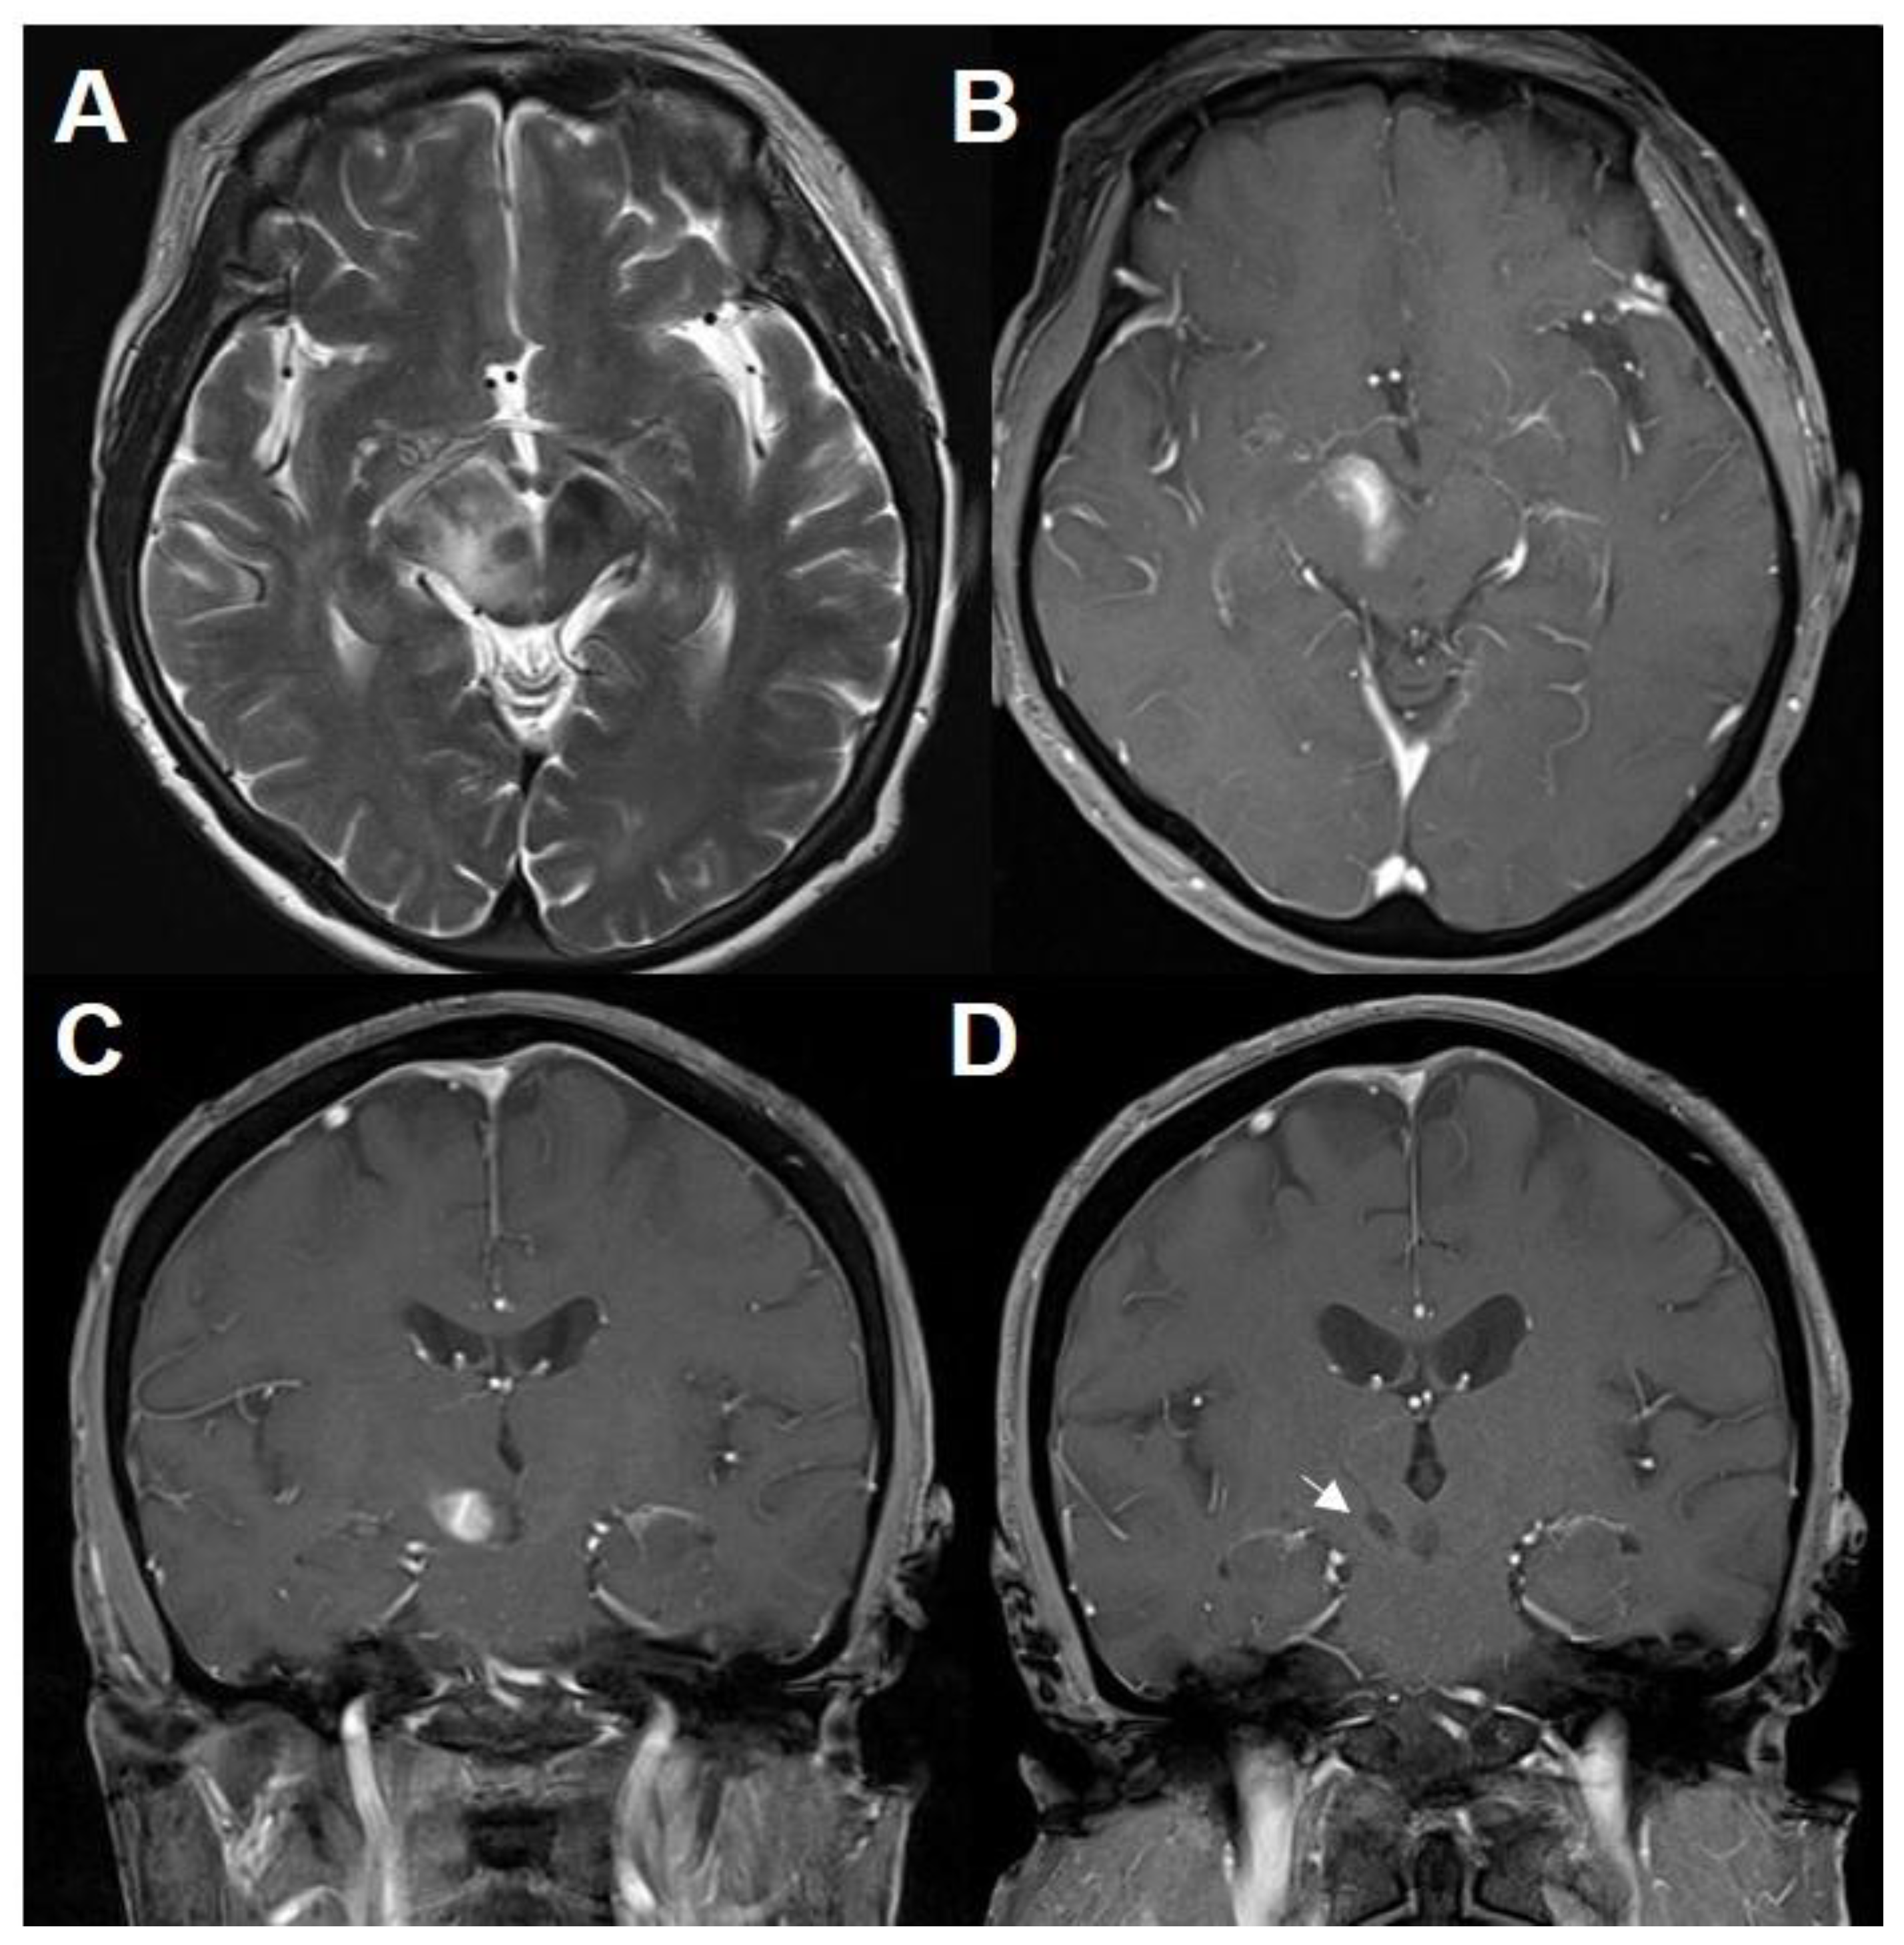

| 7 (current case) | 70/F | Facial numbness Hemiparesthesia | Homogenous enhancing lesion | Inflammatory lesion with mixed T/B-cell infiltration without demyelination | Corticosteroid | 26 | Quadriparesis Mental change | Homogenous enhancing lesions | PCNSL (B-cell) | MTX-chemotherapy | 38 mos survival |